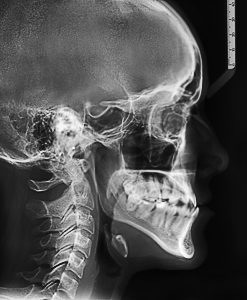

Кроме того, необходимо будет сделать рентгеновские снимки: ортопантомограмму (ОПТГ), телерентгенограммы(ТРГ). ОПТГ позволит судить о состоянии всех зубов, окружающих их костных тканях и наличии зачатков еще не прорезавшихся зубов. ТРГ — это рентгеновские снимки черепа выполненные по специальной методике, позволяющей получить снимок с размерами близкими к реальным. Так же на ТРГ различимы мягкие ткани головы (губы, нос, щеки). По ТРГ анализируется геометрия лица, выявляется характер и причина патологии, определяются допустимость и границы перемещений зубов, при этом оценивается изменение профиля лица пациента. После получения всех снимков врачу понадобится некоторое время для снятия геометрических замеров, выполнения математических расчетов и анализа результатов. Только после этого можно сделать заключение и подготовить окончательный план лечения. Возможны и другие анализы: например анализ рентгеновских снимков височно-нижнечелюстных суставов (ВНЧС). Так же перед началом лечения многие ортодонты проводят фотосъемку лица и ротовой полости. Фотография — отличный способ наглядно проследить динамику лечения и оценить достигнутый результат.